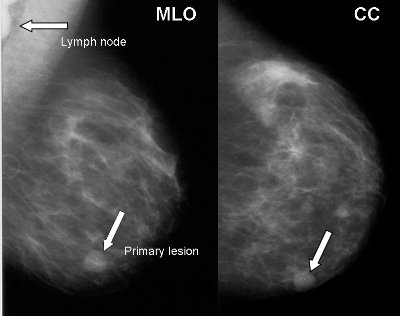

GSL- SUPRACLAVICULAR LYMPH NODE INVOLVEMENT IN LUNG CANCER

SUPRACLAVICULAR LYMPH NODE INVOLVEMENT IN LUNG CANCER By: supraclavicular lymph nodes are involved by metastatic cancer. Supraclavicular lymph nodes are International Journal of Radiation Oncology Biology and Physics attempted to answer the ... Get Doc